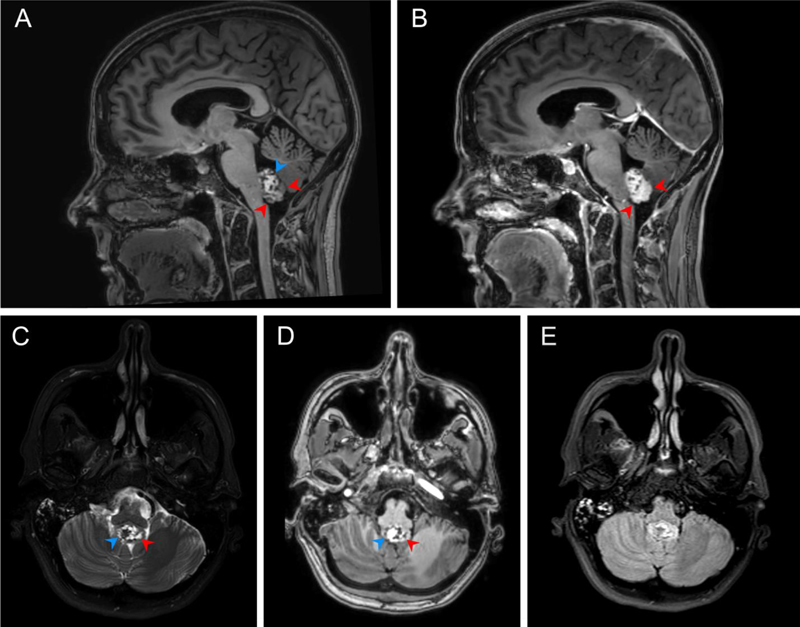

A 46-year-old Hispanic female presented with hearing loss for one year and worsening headaches and nausea for two months. Her physical examination revealed no focal neurological deficits. Magnetic resonance imaging (MRI) revealed a 2.2 x 1.5 x 2.6 cm mass involving the floor of the fourth ventricle, which showed marked intrinsic T1 hyperintensity, variable T2 signal (with areas of both hyperintensity and hypointensity), predominantly hyperintense fluid-attenuated inversion recovery (FLAIR) signal and areas of contrast-enhancement (Fig. 1). After informed consent to surgery and involvement in research (IRB ethics approval deferred as University of California, Irvine policy permits reports of up to 3 individuals), she underwent a suboccipital craniotomy for resection of the mass. Intraoperatively, the tumor appeared as a grey-brown cystic mass within the fourth ventricle that was tightly adherent to the posterior inferior cerebellar arteries and lower brainstem (Fig. 2). Radiographic gross-total resection (GTR) was achieved. The patient’s postoperative course was uncomplicated, and she was without radiographic recurrence and satisfied with her treatment at one- and three-month follow-up appointments (Fig. 3).

Figure 1. A. Sagittal pre-contrast T1 demonstrates an intraventricular mass involving the floor of the fourth ventricle and heterogenous T1 signal with areas of prominent intrinsic T1 hyperintensity (blue arrow), areas isointense to brain (red arrows), and scattered areas of low signal. B. Fat saturated sagittal post-contrast T1 demonstrates enhancement of the previously isointense portions (red arrows) with persistent areas of low signal. C. Axial fat saturated T2 at the level of the lesion demonstrates cystic areas of high T2 signal (red arrow) which correspond to low intensity of pre-contrast T1. D. A prominent low signal area on T2 is intrinsically bright on T1 (blue arrow), suggesting high protein and/or lipid contents. E. Axial FLAIR demonstrates predominantly iso- to hyperintense signal.